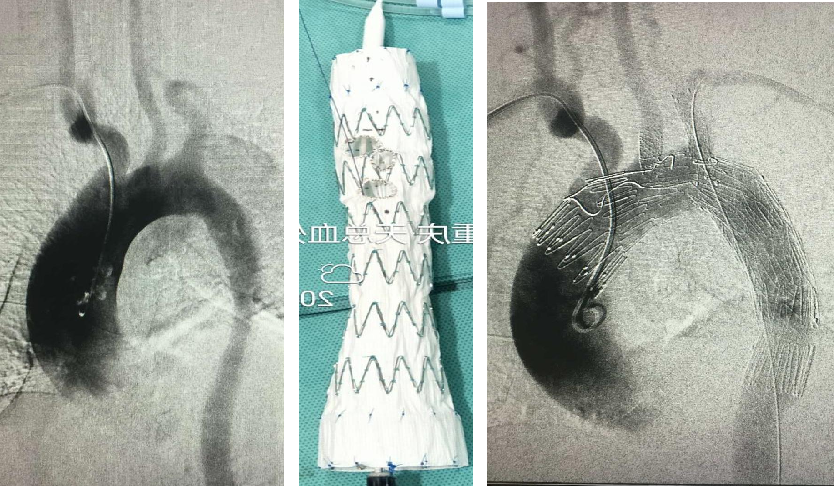

PMEG--预开窗技术

PMEG重建LSA的近中期研究结果

PMEG重建多分支的近中期研究结果

★ 分支支架技术

被视为未来弓上重建的主要方向,有外分支和内分支两种。

Castor单分支支架:中期随访(29个月),106例病例总体技术成功率98.1%,分支通畅率96.2%,再干预率2.8%,死亡率1.9%。

内分支支架:计算流体力学(CFD)分析显示其对血流干扰较外分支明显,但近期疗效相似。外分支支架解剖契合度高,减少血流紊乱和壁面剪切力。